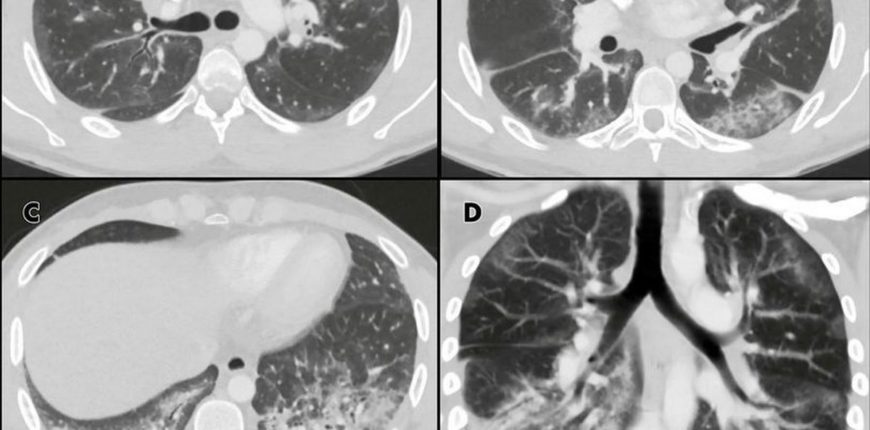

As part of a study, a US team released CT (computed tomography) X-r…